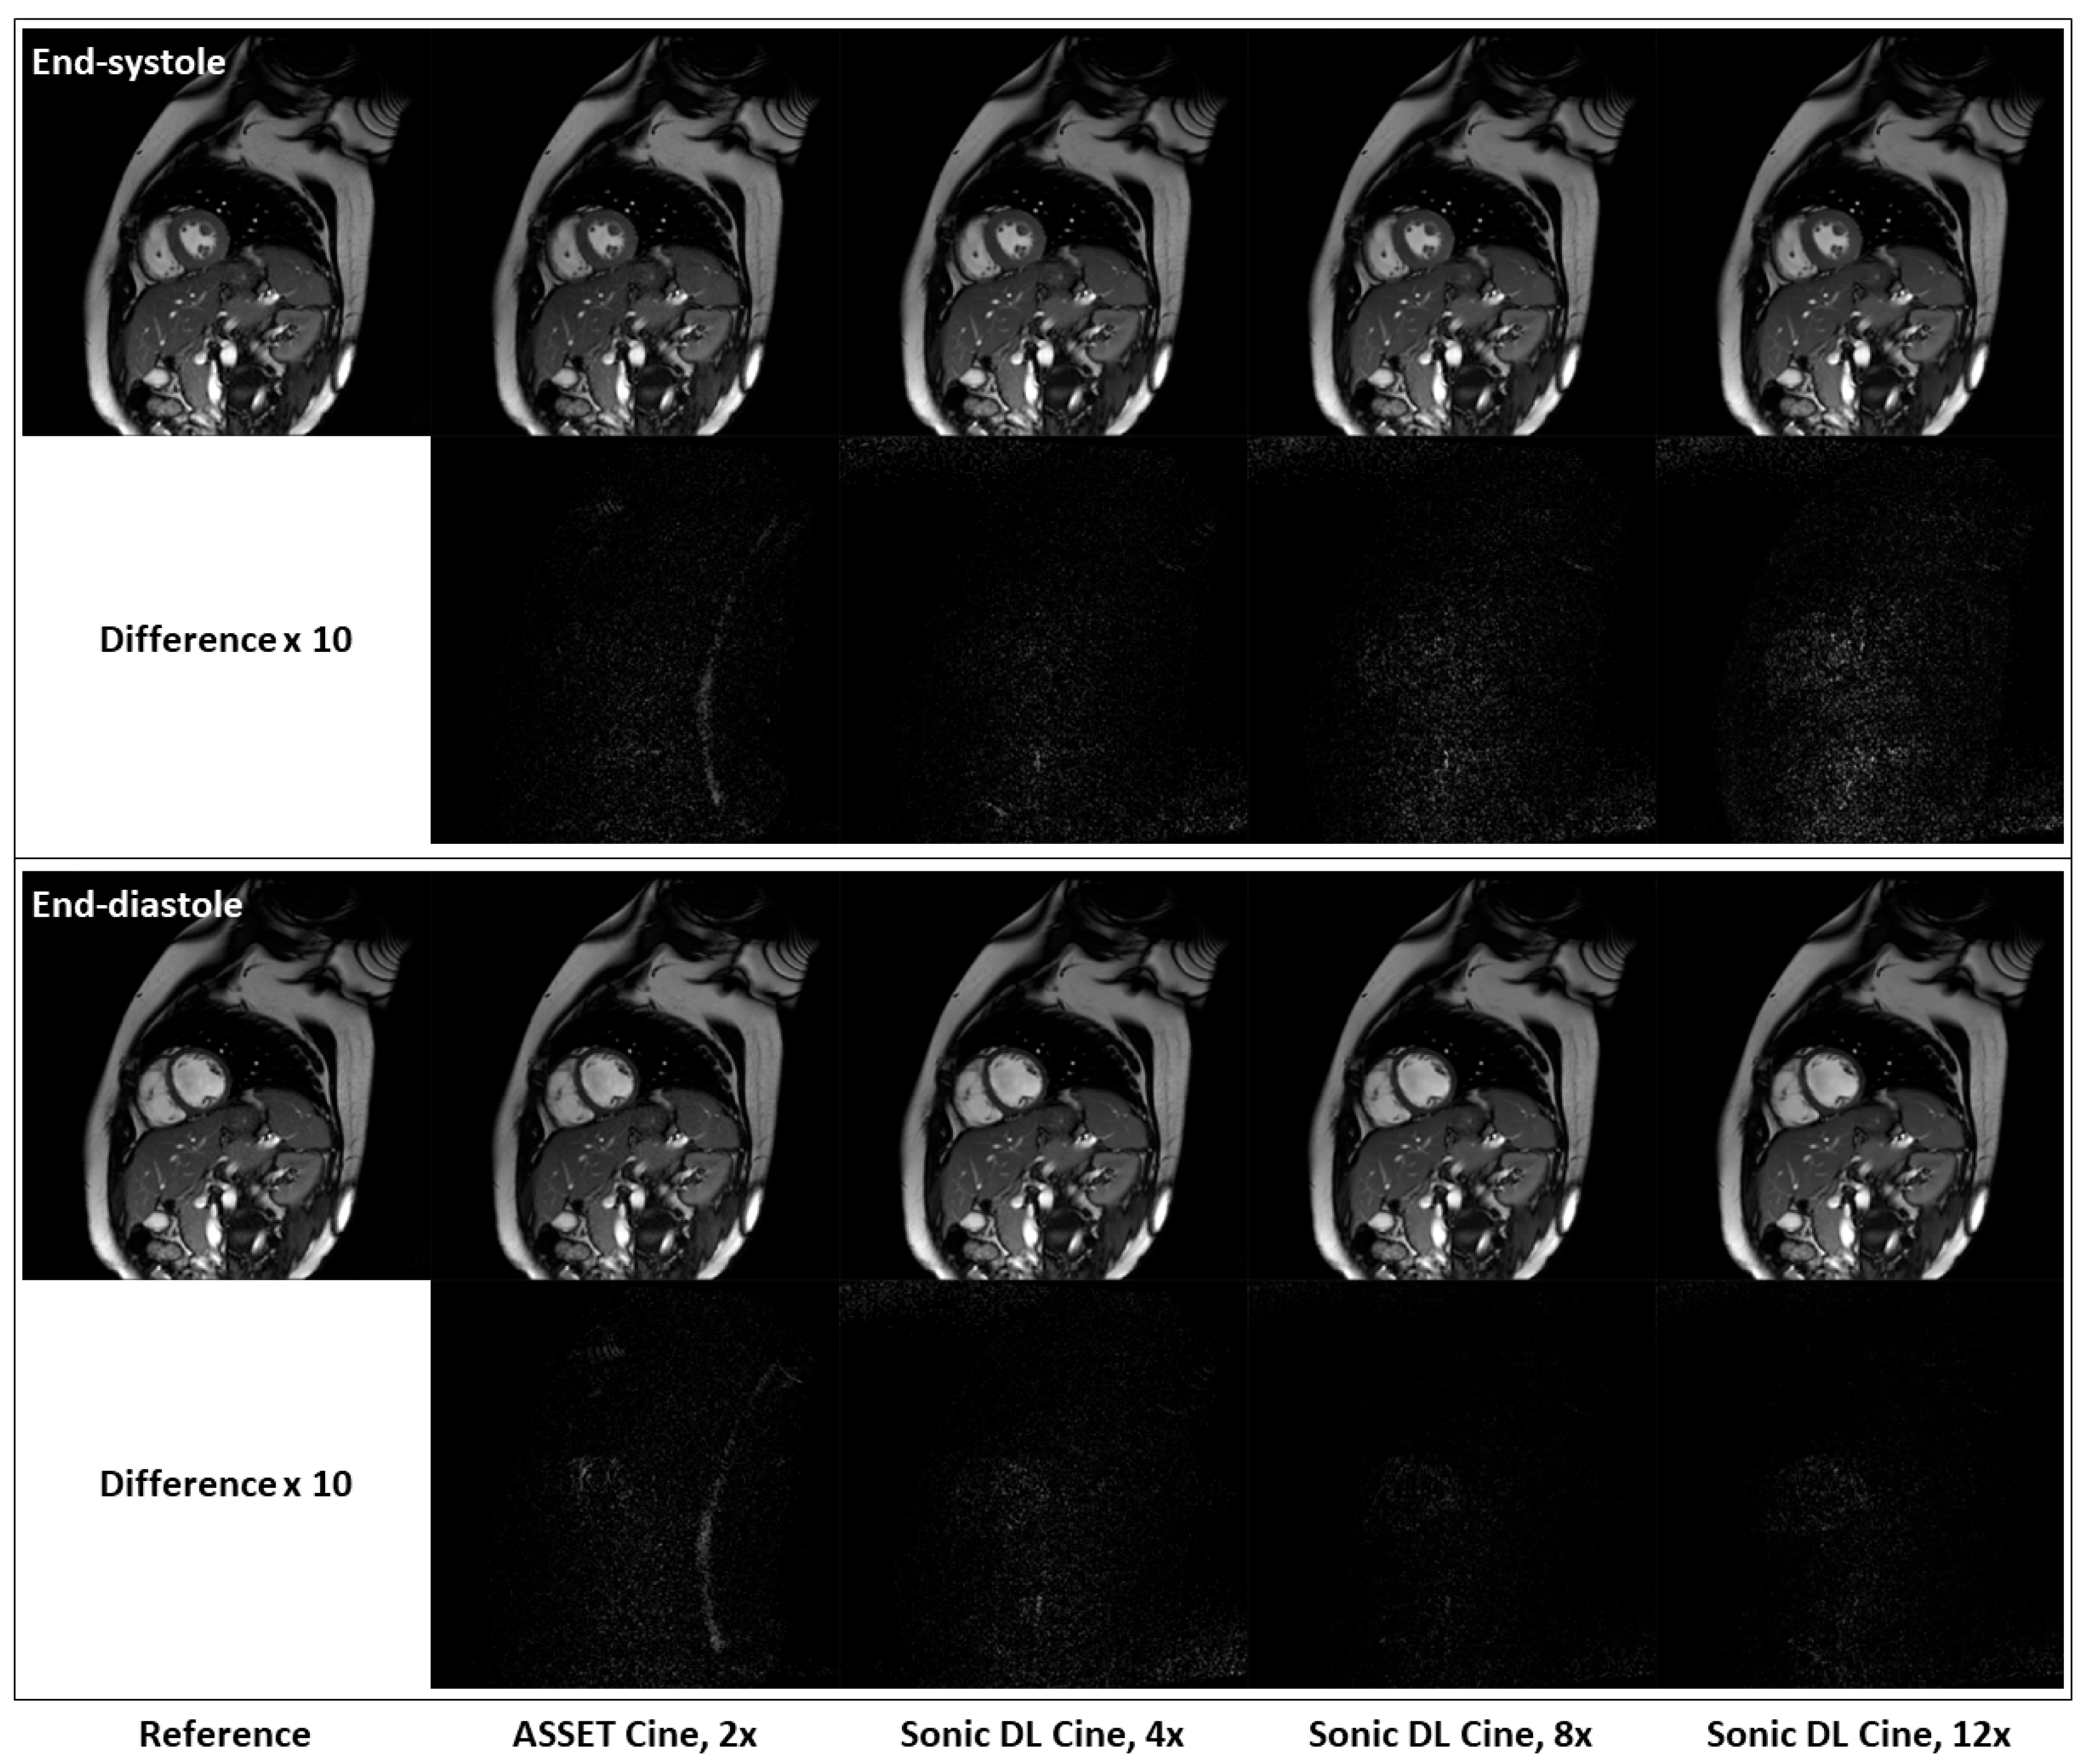

| Acceleration Factor | PSNR | SSIM | RMSE | MAE |

|---|---|---|---|---|

| 4 | 46.65 | 0.95 | 0.0047 | 0.0037 |

| 8 | 45.48 | 0.94 | 0.0053 | 0.0042 |

| 12 | 44.76 | 0.94 | 0.0058 | 0.0045 |

| Fully Sampled | Sonic DL Cine, 4× | Sonic DL Cine, 8× | Sonic DL Cine, 12× | |

| LVESV [mL] | 51.53 ± 14.24 | 51.68 ± 14.26 (p = 0.41) | 52.11 ± 14.36 (p = 0.07) | 52.68 ± 14.98 (p = 0.02) |

| LVEDV [mL] | 143.98 ± 18.32 | 143.21 ± 17.43 (p = 0.13) | 143.17 ± 17.21 (p = 0.31) | 142.52 ± 17.20 (p = 0.18) |

| LVEF [%] | 64.65 ± 6.25 | 64.37 ± 6.34 (p = 0.19) | 64.04 ± 6.67 (p = 0.08) | 63.51 ± 6.96 (p = 0.03) |

| RVESV [mL] | 73.42 ± 29.18 | 74.27 ± 29.62 (p = 0.16) | 73.93 ± 29.34 (p = 0.61) | 74.41 ± 29.37 (p = 0.56) |

| RVEDV [mL] | 172.16 ± 45.50 | 171.95 ± 45.93 (p = 0.41) | 170.06 ± 44.63 (p = 0.07) | 169.94 ± 45.23 (p = 0.01) |

| RVEF [%] | 58.47 ± 7.44 | 57.95 ± 7.29 (p = 0.23) | 57.73 ± 7.50 (p = 0.27) | 57.39 ± 7.33 (p = 0.32) |